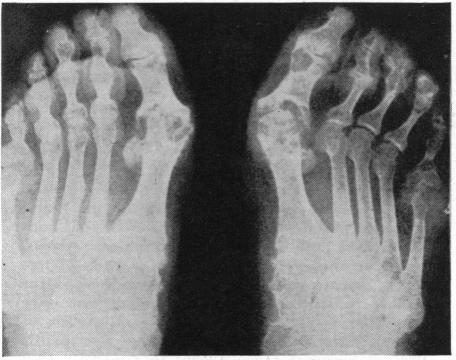

Atypical occurrence of gout (in a 37-year-old Negro woman and in an 11-year-old girl) and atypical manifestations (involvement of both hands and both feet, and of shoulders, elbows, wrists or ankles) are reported in a study of five cases. Because specific and effective therapy for gout is available, and because the diagnosis, once suspected, is readily confirmed by estimation of plasma uric acid content and by therapeutic trial, it becomes more urgent to recognize that gout is a fequently overlooked diagnosis.